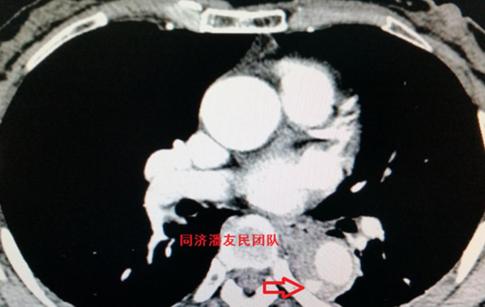

CTA同时发现脾脏破裂出血合并腹腔积液(图3)。

腹部彩超也证实脾破裂,腹腔积血(图4)。

心脏彩超、头部CT未见异常。初步诊断:车祸外伤、外伤性降主动脉夹层、脾破裂、失血性休克(早期)。